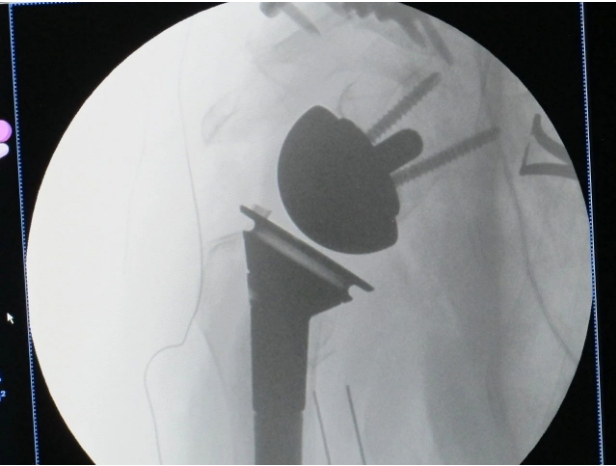

手术当天,由北京大学人民医院陈建海主任主刀。整个手术过程紧张而有序,因患者骨质疏松严重,局部骨折粉碎,随时要避免副损伤的发生,每一步都充满了挑战和考验,但陈主任凭借其精湛的技术和丰富的经验、出色的专业技能与我院创伤骨科团队默契配合、平稳顺利的为患者实施手术,成功配合完成了这一高难度的手术。

反肩关节置换术(Reverse Total Shoulder Arthroplasty, RTSA)是一种复杂而精细的手术,其主要目的是在肩部损伤严重的老年病人或肩袖严重撕裂无法修复的情况下,通过反向安装人工肩关节来恢复患者的肩关节功能。与传统的肩关节置换手术不同,反肩关节置换术将人工肱骨头置于肩胛盂上,而肩胛盂假体则固定于肱骨近端,从而实现肩关节旋转中心的内移和下移,进而增大三角肌的力臂,形成稳定的力学支点。